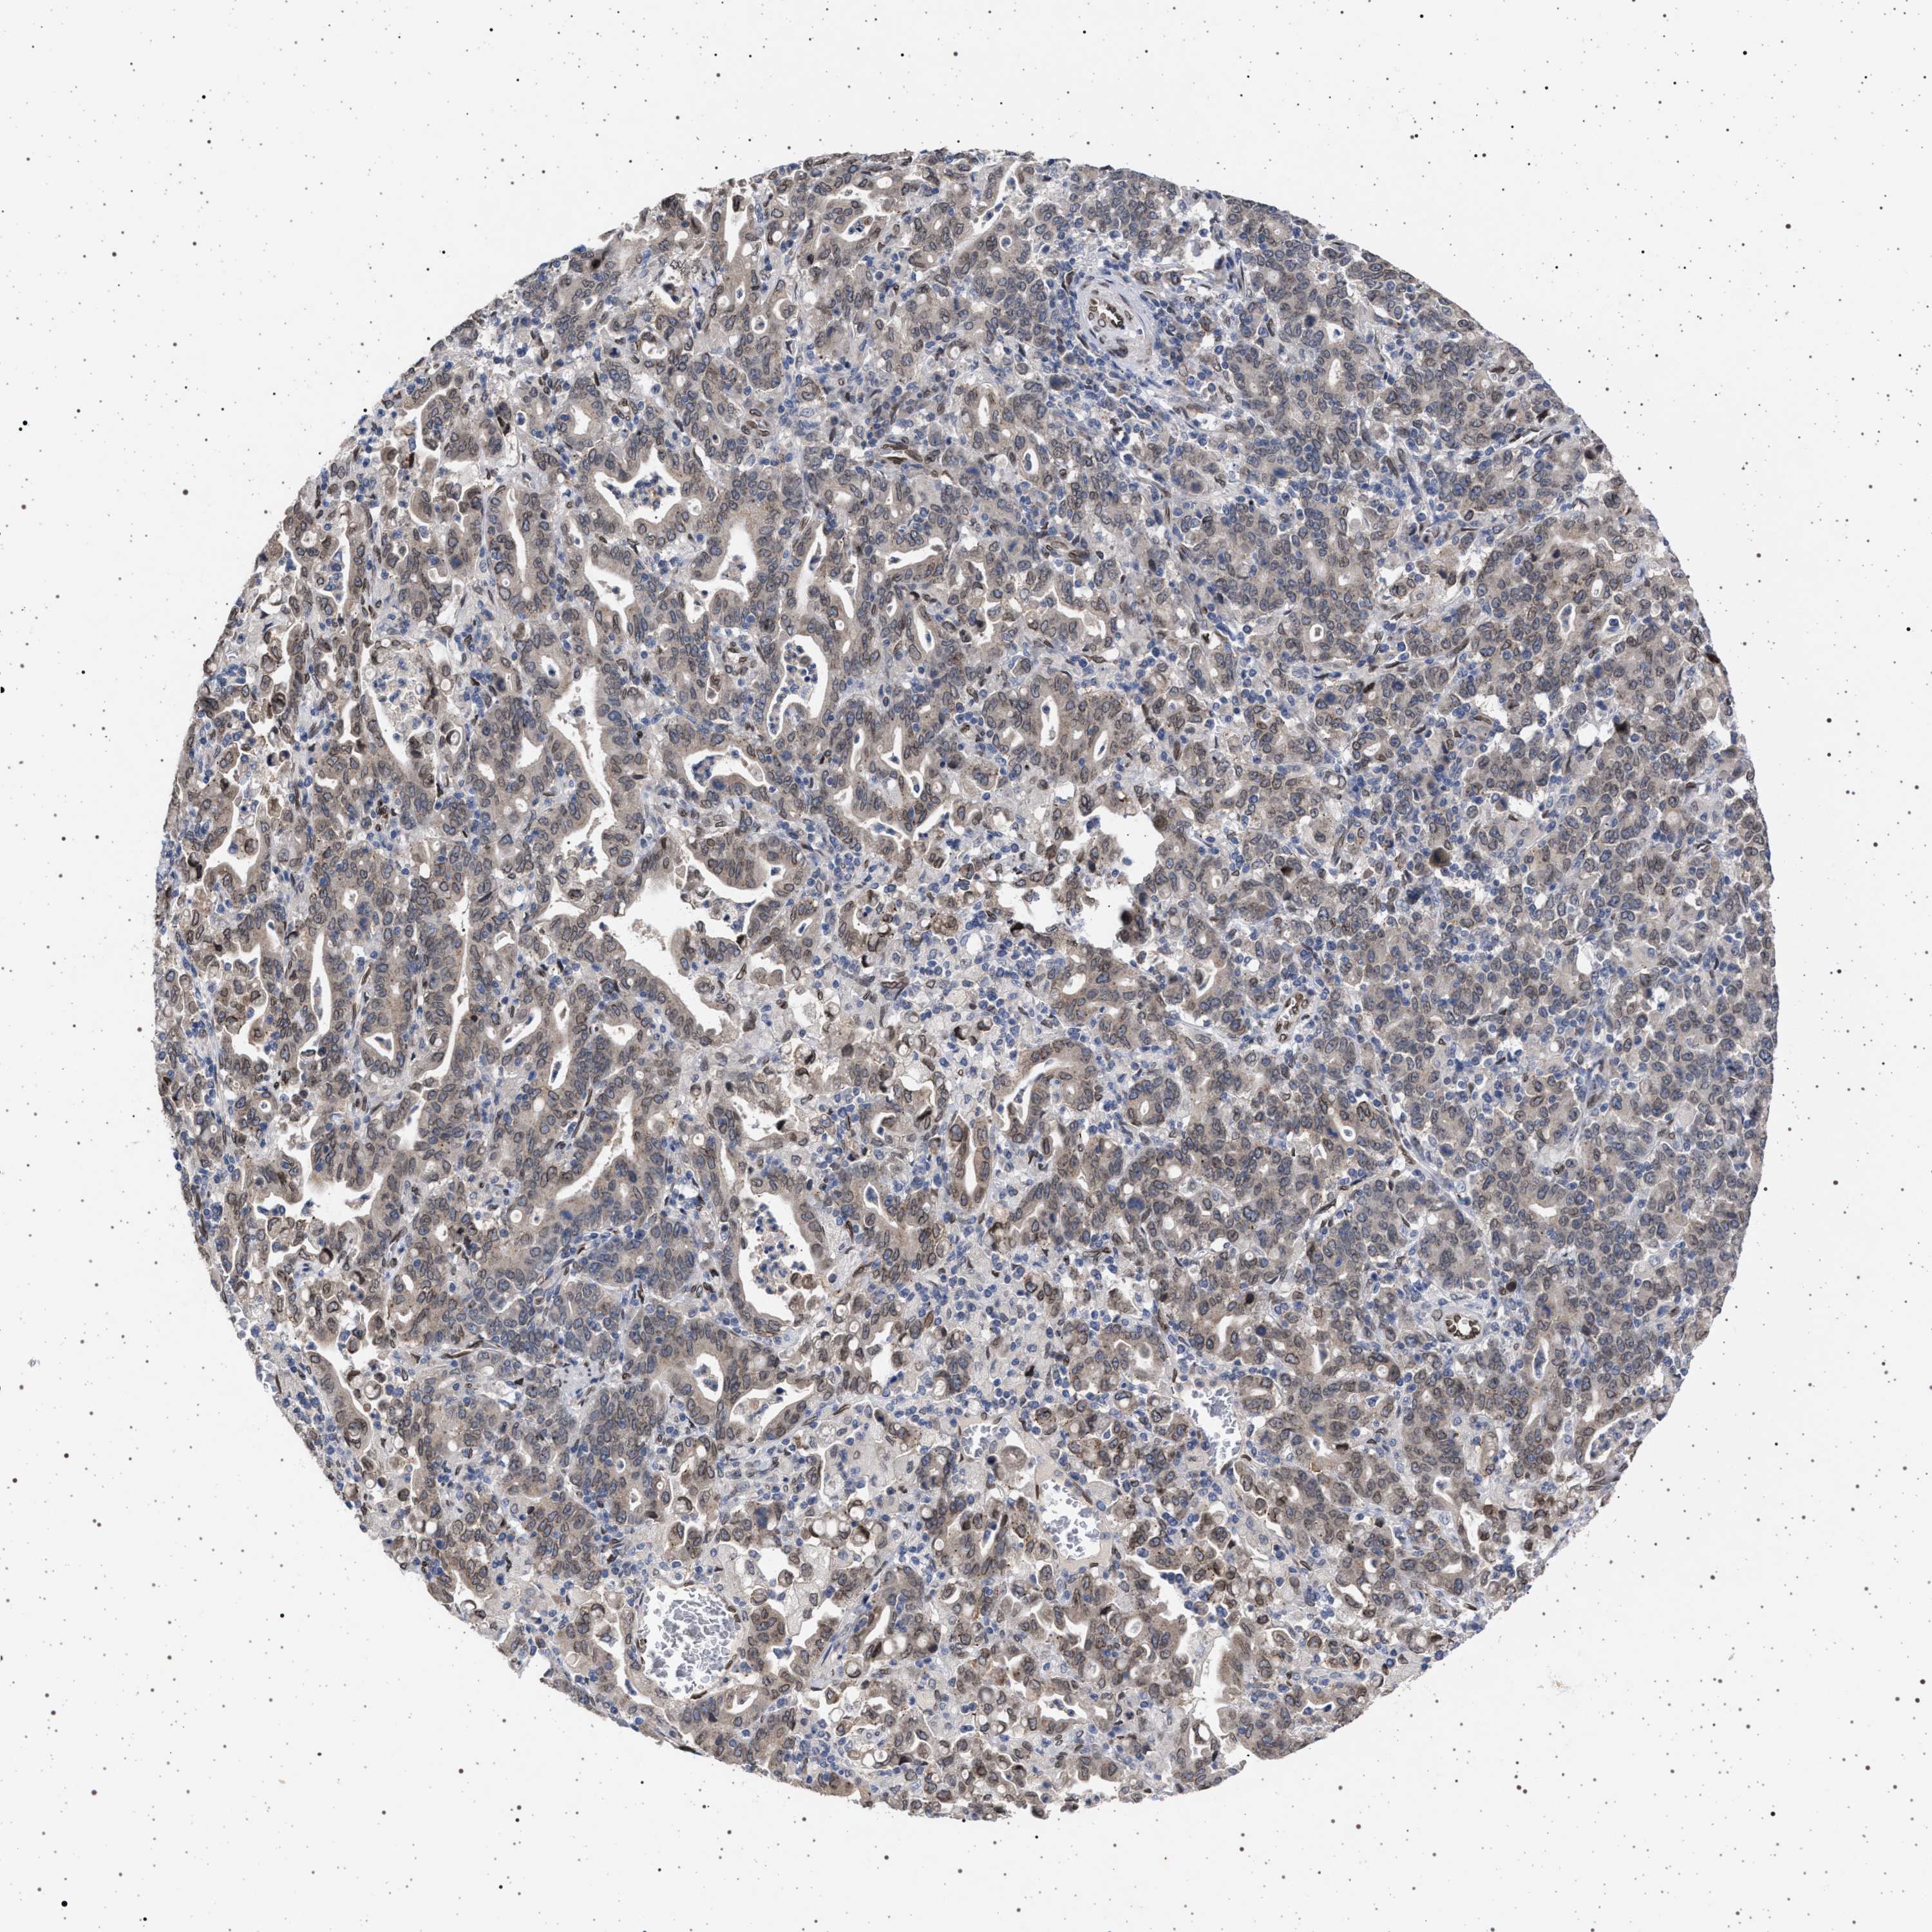

STOMACH CANCER - Protein expressioni

A mouse-over function shows sample information and annotation data. Click on an image to view it in a full screen mode. Samples can be filtered based on level of antibody staining by selecting one or several of the following categories: high, medium, low and not detected. The assay and annotation is described here.

Antibody stainingi

Antibody staining in the annotated cell types in the current human tissue is reported as not detected, low, medium, or high, based on conventional immunohistochemistry profiling in selected tissues. This score is based on the combination of the staining intensity and fraction of stained cells.

Each image is clickable and will lead to virtual microscopy that enables deeper exploration of all samples and also displays staining intensity scores, fraction scores and subcellular localization as well as patient and tissue information for each sample.

Antibody HPA019486

Antibody HPA021517

Staining

High

Medium

Low

Not detected

Intensity

Strong

Moderate

Weak

Negative

Quantity

>75%

75%-25%

<25%

None

Location

Nuclear

Cytoplasmic/membranous

Cytoplasmic/membranous,nuclear

Adenocarcinoma, NOS